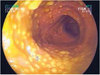

COLITE PSEUDOMEMBRANOSA